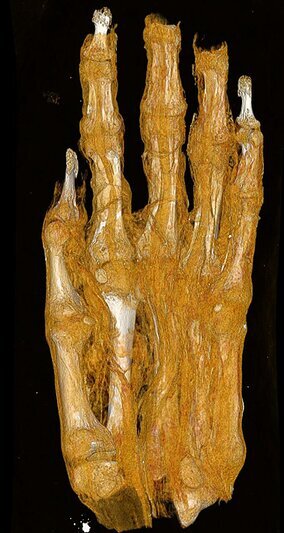

Отдельный интерес вызвал объект, который ранее ошибочно интерпретировался как голова, а затем как возможная мумия птицы. Повторная КТ показала, что это человеческая ступня взрослого человека.

Также изучается мумифицированная рука, по которой специалисты пытаются определить возраст, пол и биологический статус человека на основе костных характеристик.